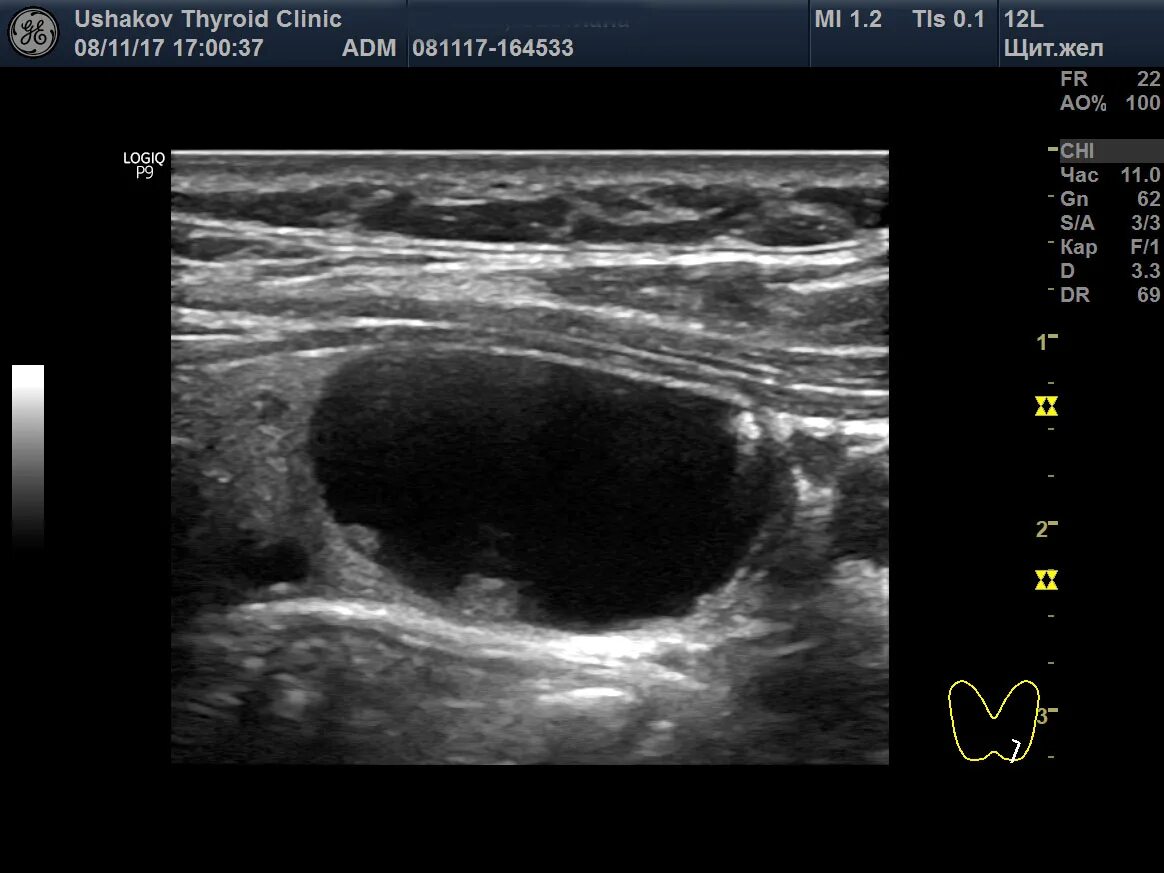

Солидное образование форум